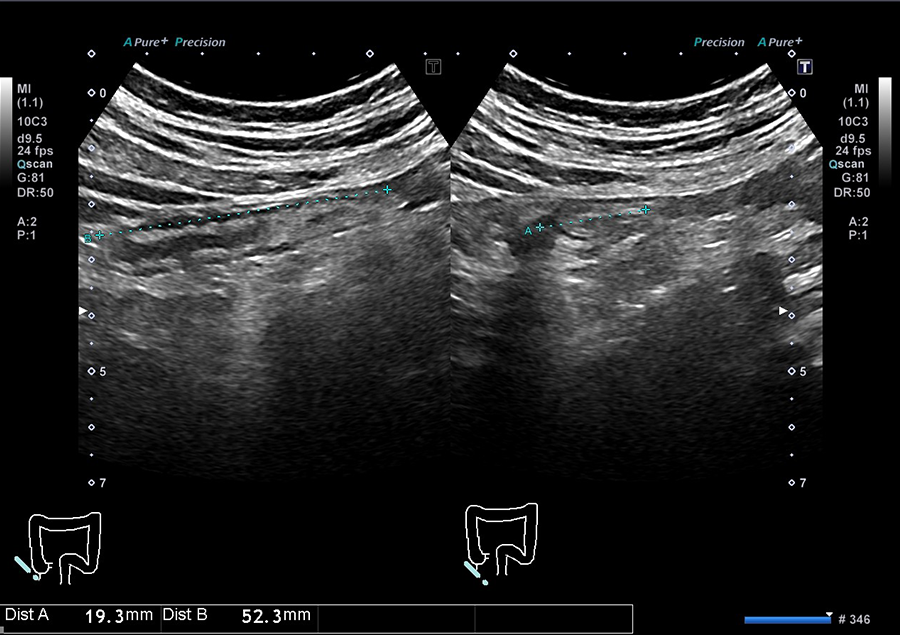

02.最新の超音波診断装置を導入

当院では、キヤノンメディカルシステムズ株式会社の超音波診断装置「Aplio a Verifia」を導入しています。

- ノイズを低減し、クリアな画質で病変を検出

- 従来の腹部エコーに比べ、広範囲を一度に撮影可能で、病変の位置がより分かりやすく確認できます

- 送信・受信技術(Advanced Sync Pulser と Advanced Beam Receiver とMulti-Harmonic Compounding)により、高精細な画像を提供

- 低流速血流の観察に適したSMI で、病変を詳細に観察

高精細な画像と優れた解析技術により、正確に観察することが可能です。